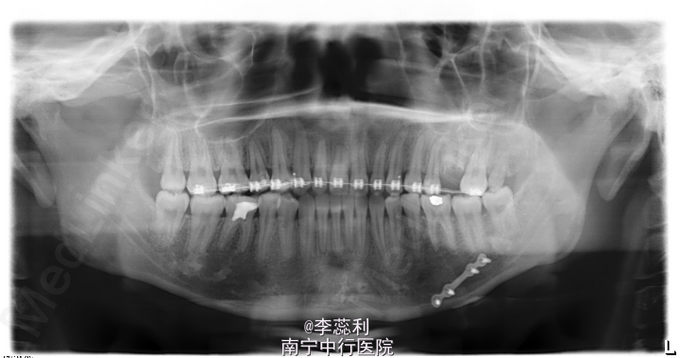

青年女患者,正颌术后1年,要求拆除钛板,患者于1年前因下颌偏颌畸形入院,于2014年6月18日行“左侧下颌升支矢状劈开后退术+去骨皮质术+骨内坚固内固定术”

双侧颌面部基本对称,双侧颞下颌关节动度正常,无疼痛及弹响,双侧颞下颌关节区无明显压痛,开口型“↓”,开口度5.9cm。口内检查:左下下颌前庭沟见手术瘢痕,上颌牙列正畸托槽固定在位,下颌正畸托槽拆除,前牙浅覆合浅覆盖,下颌中线偏右2mm,双侧后牙咬合关系尚可。全景片示左下颌骨固定钛板位于35,36,37根尖方向